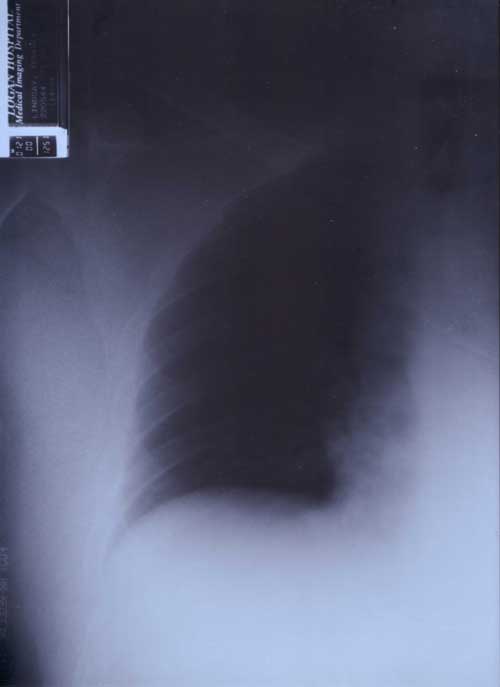

X Rays

21st January 2000